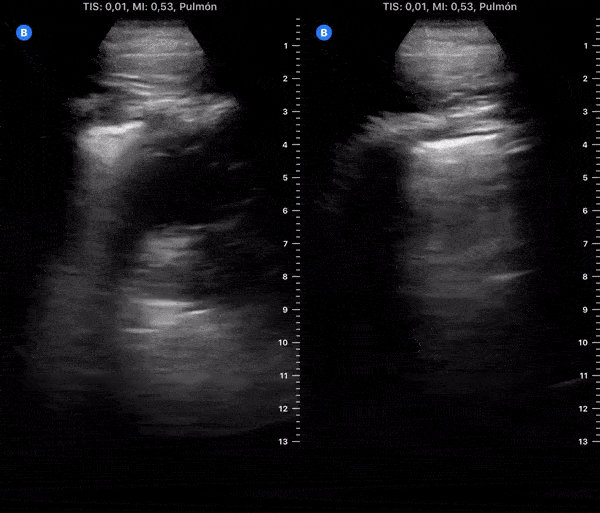

COVID 19 Lung US Disease Progression - Day 12

Day 12 after #COVID diagnosis. Better, main symptoms cough, nausea & diarrhea. No dyspnea or red flag symptoms. No fever. SpO2 98%. #POCUS update: Subpleural consolidations resolving, thick pleura & B-lines, small effusion. @yaletung